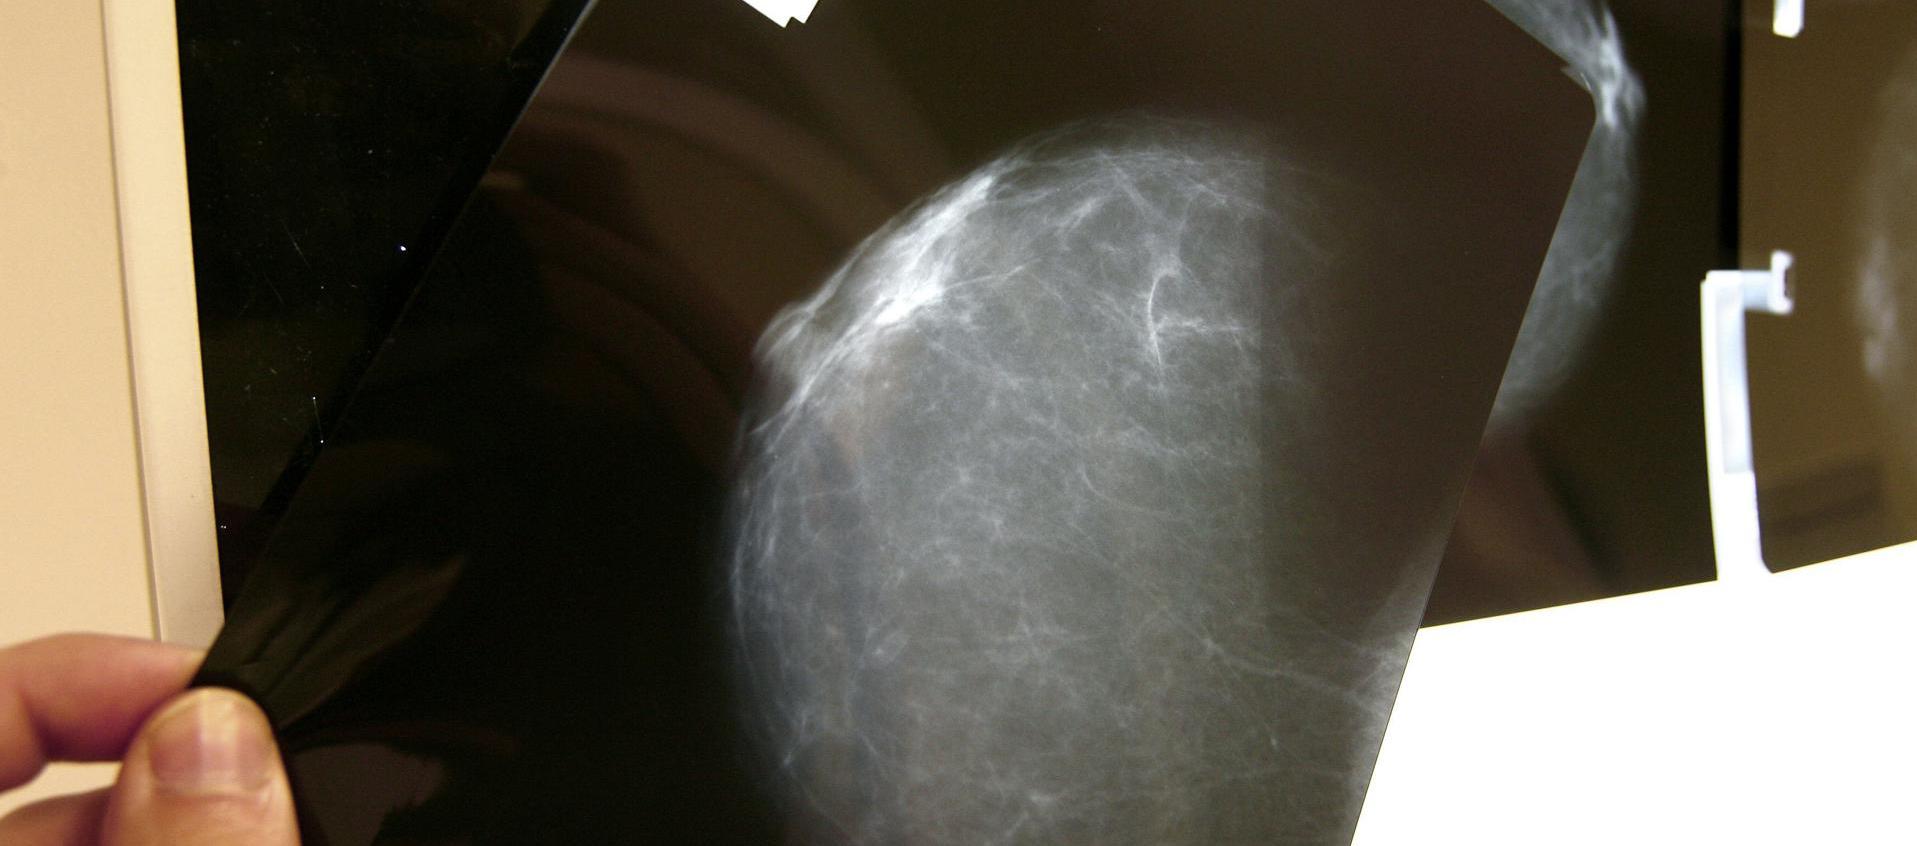

Fotografía de archivo de una prueba radiológica de mama.